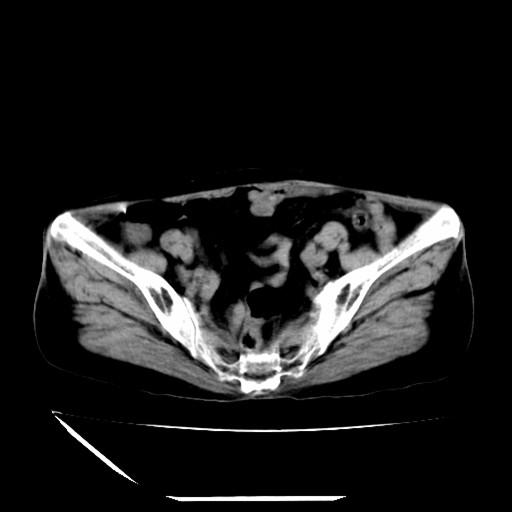

标题: CT16840:女-63岁,下腹部疼痛, [打印本页]

标题: CT16840:女-63岁,下腹部疼痛,

补充资料:血象是13.5,临床拟诊阑尾炎

本人诊断是右肾周围炎,阑尾炎,盆腔少许积液!

诊断右肾周围炎是因为我图像没有发完,诊断阑尾炎是因为相当于阑尾区连续两个层面可以看到增粗的阑尾显影。

支持阑尾炎!局部腹膜增厚,脂肪密度增高。应该手术治疗。